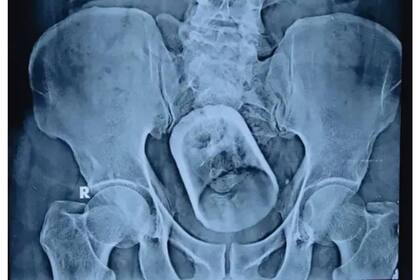

En un hospital de Bihar, India, un paciente llegó esta semana con estreñimiento y un fuerte dolor abdominal. A la hora de indagar en los motivos de su dolencia, los médicos decidieron hacerle una radiografía que arrojó un resultado sorprendente.

Resulta que esta persona de 55 años tenía en su estómago un vaso que se había tragado accidentalmente mientras tomaba té, lo cual le generó una “perturbación grave” en sus intestinos. El siguiente paso fue resolver cómo extraerían el objeto. Primero, intentaron hacerlo a través del tradicional método endoscópico. Sin embargo, los doctores no lograron extirpar el vaso, por lo que tuvieron que pasar a la segunda alternativa: una intervención quirúrgica.

Los profesionales dudaron de que el paciente se hubiera tragado el vaso “accidentalmente”, puesto que el tamaño del objeto insertado es demasiado grande para que pueda pasar por el tubo de alimentación humano. “Cómo entró en el cuerpo del paciente sigue siendo un misterio”, dijo Mahmudal Hasan, jefe del equipo médico a cargo de la cirugía. Tras la operación, el paciente se recuperaba sin mayores complicaciones. Afortunadamente, se encuentra actualmente estable después de su curioso percance.